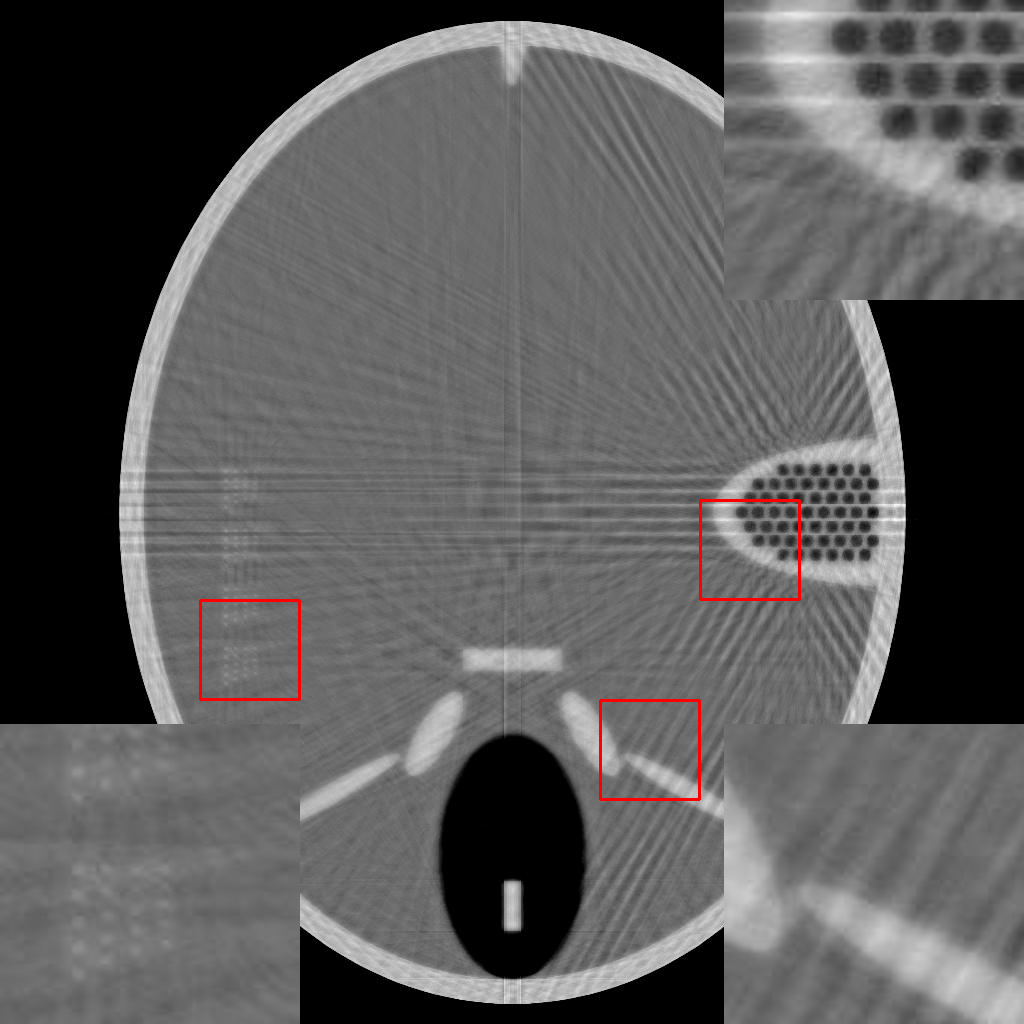

To demonstrate the efficacy of the RBP connection and show the details of the RBP-DIP’s reconstruction process, the procedure of a limited-angle CT reconstruction is shown in Fig.2. Its first row illustrates the results of reconstruction across different iterations, whereas the second row presents the respective inputs fed into the U-net, which are updated through the RBP connection. Here, the number of views is set to , uniformly distributed from to . This scenario presents a challenging limited-angle CT reconstruction problem.

In the first iteration, as depicted in Fig.2a, the input image undergoes an update via the RBP connection prior to being fed to the U-net. Thus, this input is the normalized first iteration output of the implemented IR algorithm (normalized back projection image in our case). The output appears completely randomized since the entire neural network is randomly initialized.

In the 10th and 20th iterations (Fig.2b and Fig.2c), the DIP property effectively expedites the recovery of the object over its support. Of note are lack of artifacts commonly caused by having missing views in the data. The input images highlight the region which can be relatively accurately reconstructed by conventional IR methods. This can be used to guide the model in the later iteration. In our experiment, the model capitalizes on the input images more when reconstructing the upper-left and lower-right segments of the image, while relying predominantly on the DIP property for the reconstruction of the upper-right and lower-left parts.

In the 2000th iteration, as depicted in Fig.2d, the reconstruction result becomes relatively artifact-free. At this stage, the network input primarily emphasizes the edges to help the method improve the supporting area. Moreover, the RBP connection can rectify artifacts specific to convolutional neural networks. Evidence of this can be observed in the second row of Fig.2c, Fig.2d, and Fig.2e, which display distinct horizontal and vertical patterns. These patterns are mainly caused by the convolution operation in the U-net. In other words, the DIP and RBP parts of the proposed framework are able to mutually rectify each other’s errors. Consequently, a high-quality reconstruction result is attainable, as shown in Fig.2e.

For a more direct comparison, the three aforementioned methods are tested on the Forbild phantom under few-view ( views which are evenly distributed from to ), and limited-angle ( views which are evenly distributed from to ). From Fig.3, it is clear that both the DIP and RBP-DIP exhibit superior performance compared to ASD-POCS, particularly in the reconstruction of detailed structures. The magnified views of these structures are available in the bottom left and top right corners of these images. In contrast to DIP, RBP-DIP is better at mitigating some neural network-specific artifacts, with the corresponding magnified view presented in the bottom right corner of these images.